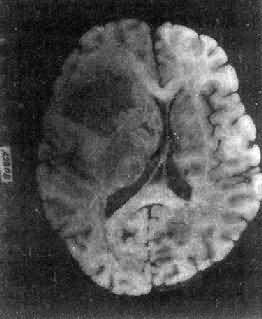

肉眼观,肿瘤呈球形,分叶状或不规则形,质实或硬,边界清楚,周围脑组织受压成凹陷切迹(图16-27)。少数肿瘤呈斑块状覆盖较广泛区域,甚至整个脑半球,称为斑块型脑膜瘤。肿瘤质地硬,切面灰白色,呈颗粒状、条索旋涡状,有的质地似砂砾样,乃由于有多量砂粒体存在。

脑膜瘤

图16-27 脑膜瘤

大脑两半球间有一近似球形肿瘤,边界清楚,周围脑组织受压萎缩